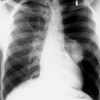

¿Qué proyección es la siguiente?

PA